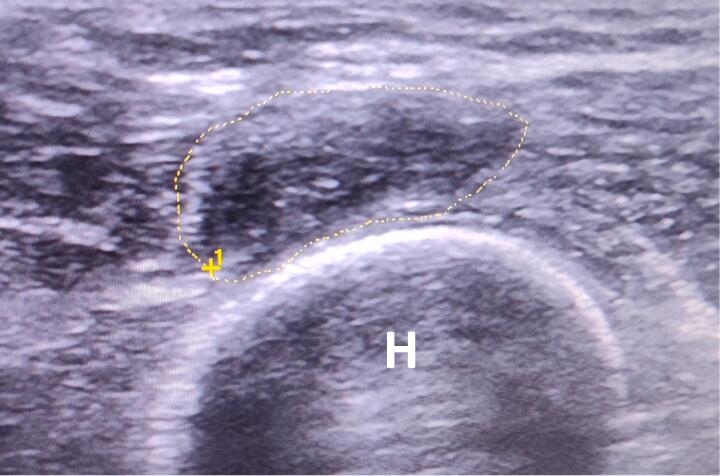

4.1 Ecografía

- 🔹 Prueba de elección. Debe realizarse con transductores lineales de alta frecuencia (10-18 MHz).

- 🔹 Hallazgo característico: masa hipoecoica, de forma ovalada o fusiforme, en continuidad con el extremo del nervio seccionado. Los bordes pueden ser bien definidos o infiltrativos. El tamaño es variable (desde pocos milímetros hasta varios centímetros).

- 🔹 Doppler: puede mostrar flujo vascular interno (a diferencia de otros tumores neurales).

- 🔹 Dinámica: la ecografía permite valorar la movilidad del neuroma y su relación con las estructuras vecinas (prótesis, tendones).

Hallazgo ecográfico característico